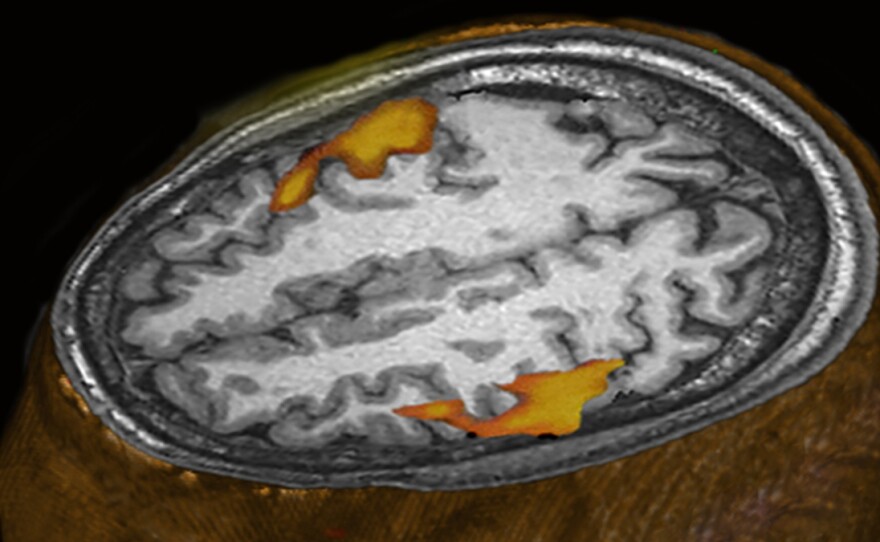

An MRI scan of a person listening to music shows brain areas that respond. (This scan wasn't part of the research comparing humans and monkeys.)